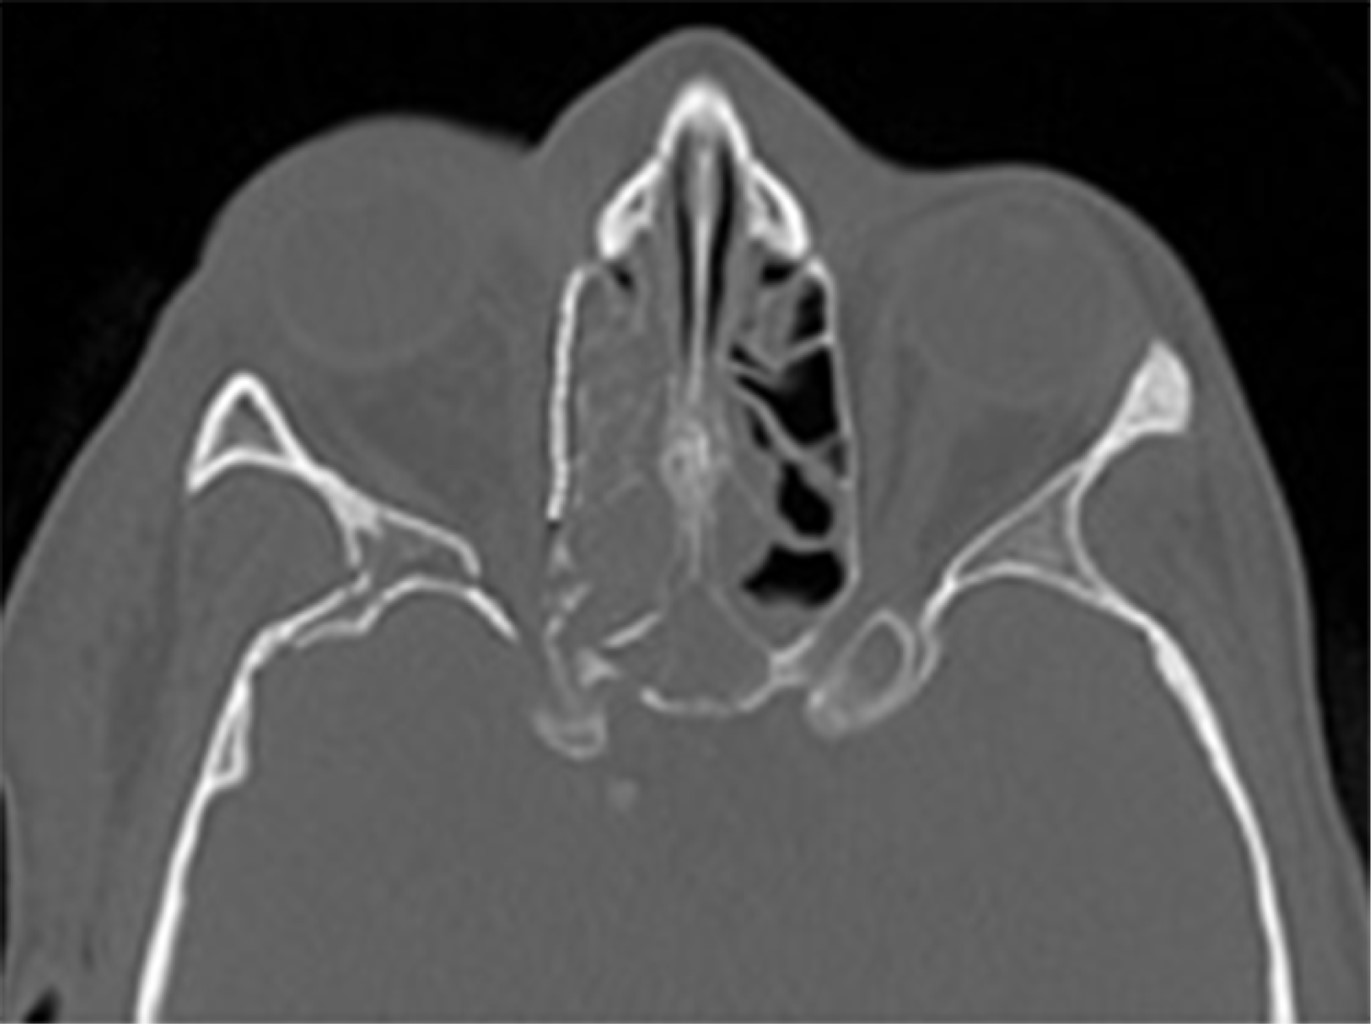

CASO TRES

Paciente masculino, 30 años, víctima de accidente de motocicleta, sin protección, con colisión frontal con otra motocicleta, recibió atención del equipo de Cirugía Oral y Maxilofacial y Traumatología del Hospital da Posse en la ciudad de Nova Iguaçu, Río de Janeiro. Presentaba un traumatismo en la región orbitaria derecha, que evolucionaba con signos clínicos de enoftalmos, distopía y oftalmoplejía en mesial y supraversión.

La tomografía de la cara muestra afectación de la pared orbital medial que a su vez afecta al suelo orbital y a la región de la zona clave (Figura 9).

Se realiza abordaje bicoronal y subtarsal para la resolución del atrapamiento de tejidos blandos, de la musculatura del recto inferior y medial así como la reducción de la fractura. Se utiliza para la reconstrucción una malla orbital para el correcto reposicionamiento y reconstrucción de la zona clave, así como del contenido orbital. La tomografía computarizada del postoperatorio inmediato mostró la reconstrucción de la órbita mediante malla y sistema de fijación con tornillos de 1.5 mm; se observa el correcto contorno de la órbita, el retorno de su contenido y forma así como la importancia de la adaptación posteromedial y la correcta reducción y reconstrucción de la zona clave para el éxito y resolución del caso (Figuras 10, 11 y 12). Seguimiento de 60 días postoperatorios sin presentar restricciones de movimiento ocular, distopía y diplopía, retorno de la agudeza visual y edema leve en región periorbitaria.